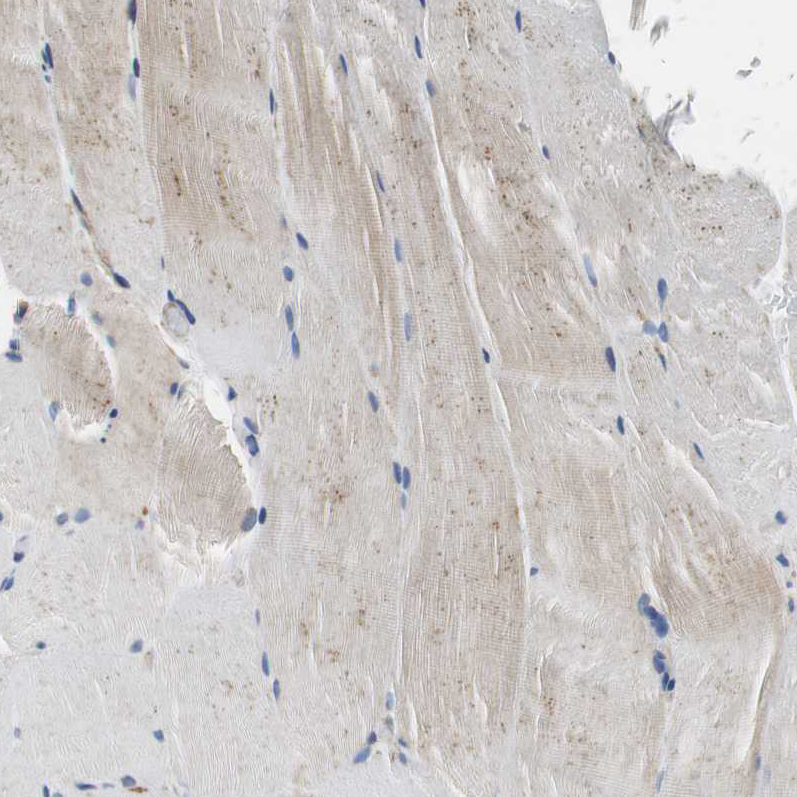

Immunohistochemistry analysis in human duodenum and pancreas tissues using HPA006311 antibody. Corresponding GSTK1 RNA-seq data are presented for the same tissues.